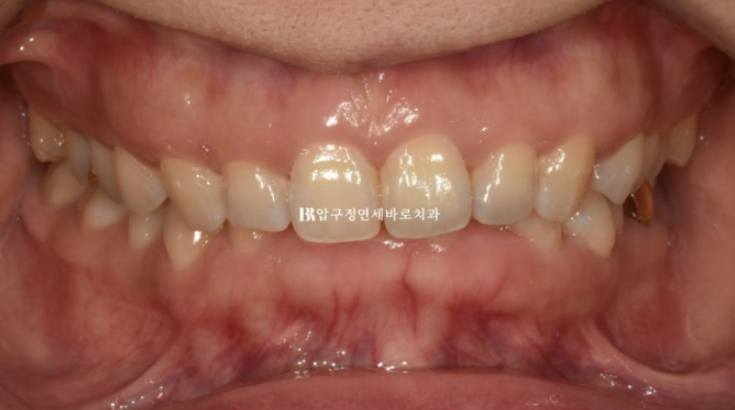

24년 1월 교정치료를 위해 내원하신 분입니다.

예전에 브라켓 철사 교정치료를 이미 했고 여러가지 불편한 점을 고치기 위한 재교정입니다.

교합평면이 기울어져 있습니다.

이렇게 평면이 기울어져 있으면 앞니도 그에 맞춰 기울어져 있는 경우가 많습니다.

윗니가 아랫니를 많이 덮어 아랫니가 전혀 보이지 않을 정도의 심한 과개교합 입니다.

예전 교정치료의 흔적으로 위 앞니에는 철사유지장치가 붙어있습니다.

철사 유지장치가 여러 조각이 나있는 이유는?

과개교합 때문입니다.

과개교합이 남은 채로 교정치료가 마무리가 되면 철사유지장치가 아랫니와 닿아 불편하고 자꾸 떨어지고 문제가 생깁니다.

과개교합은 이렇게 교정 완료 후 재발 가능성과 유지관리에 큰 장애가 됩니다.

반드시 해결하는 것이 좋습니다.